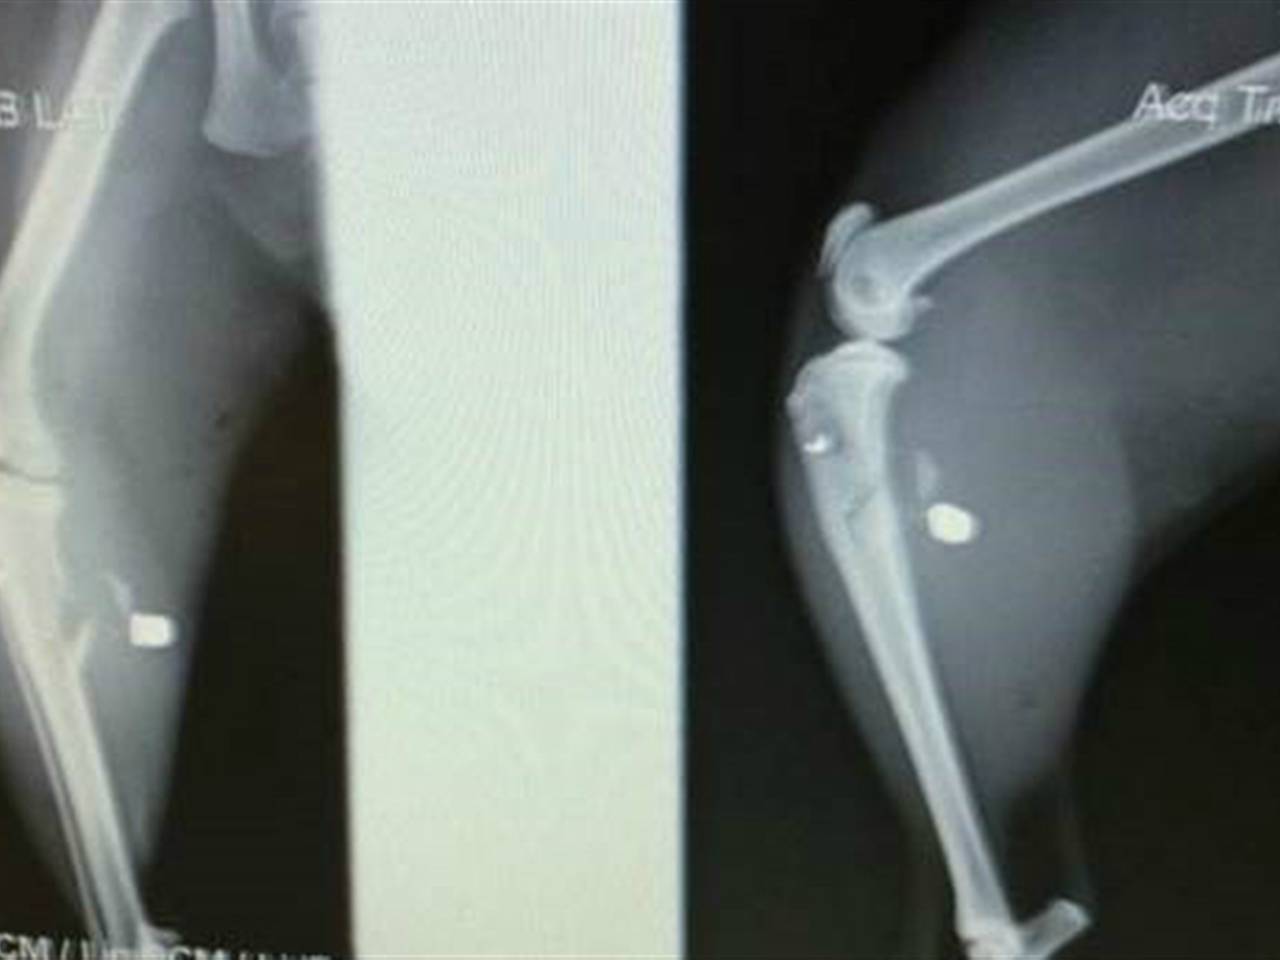

De kat werd met een schot hagel in zijn achterpoot geraakt: "We hebben echt geluk gehad, iets hoger en zijn knie was verbrijzeld en iets hoger en we hadden hem misschien in moeten laten slapen."